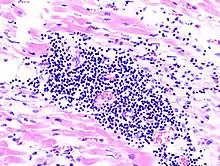

Acute myocardial infarction

Der Myokardinfarkt muss mind. 6 - 12 Stunden überlebt werden, bevor er morphologisch sichtbar wird!

Mikro: Koagulationsnekrose, Einblutungen. Die Myozyten zeigen eine verstärkte Eosinophilie und Kontraktionsbanden quer durch die Herzmuskelfasern. Typische Zellparameter wie Querstreifung, Zellkerne und Zellgrenzen gehen verloren. Das Infarktareal wird von einer Hyperämischen/hämorrhagischen Randzone begrenzt. Im Verlauf zunehmende leukozytäre Demarkation und Phagozytose des nekrotischen Gewebes, sowie Einwanderung von Fibroblasten mit Ausbildung eines narbigen Ersatzgewebes.

![]() Akuter Myokardinfarkt, H&E. |